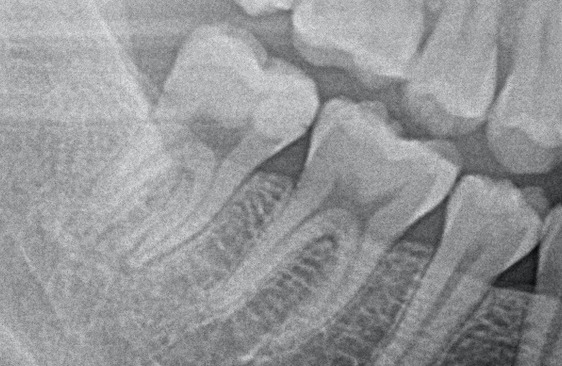

こちらが初診時のレントゲン写真になります。

レントゲン写真を見ると、以前治療した詰め物(コンポジットレジン)がかなり神経まで近接していることが分かりました。おそらく非常に大きな虫歯治療を数年前にしたものかと思われます。

また、レントゲン写真を細かく見ると、詰め物の下に黒い影があり、虫歯になっていることも分かります。昔の詰め物の隙間から虫歯が再発し、細菌が神経に到達してしまったことで、歯の神経が炎症を起こしている状態です。歯科用語では歯髄炎という状態になり、自発痛(ズキズキした痛み)が出てしまっているので、残念ながら神経を取る治療(抜髄)が必要となります。